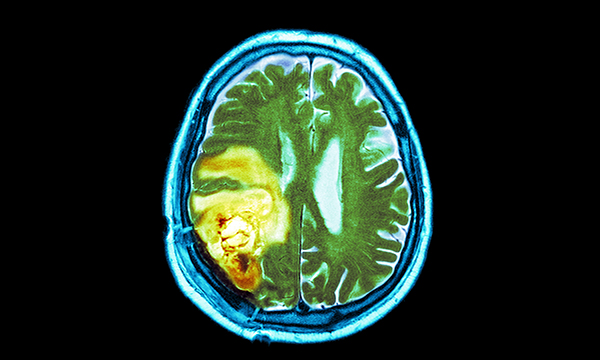

Scientists have found 13 new genetic errors associated with an increased risk of developing glioma, the most common form of brain cancer.